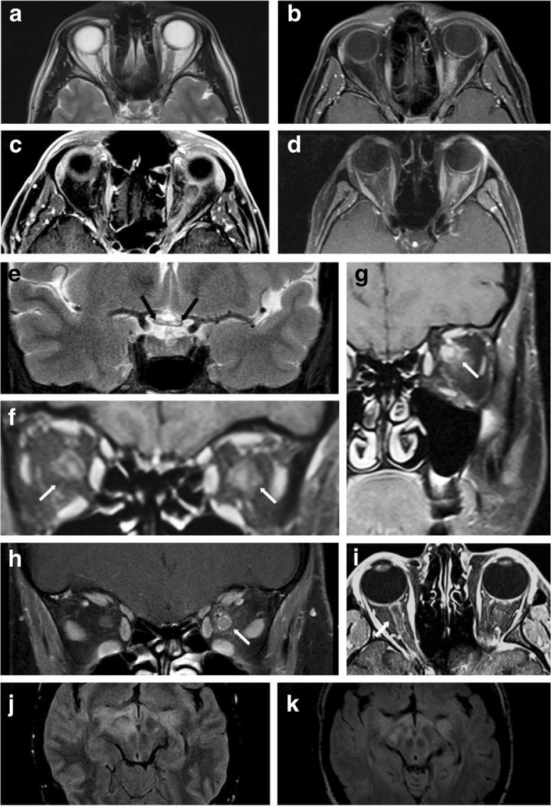

眼和眼眶的影像学诊断

▎视神经病灶